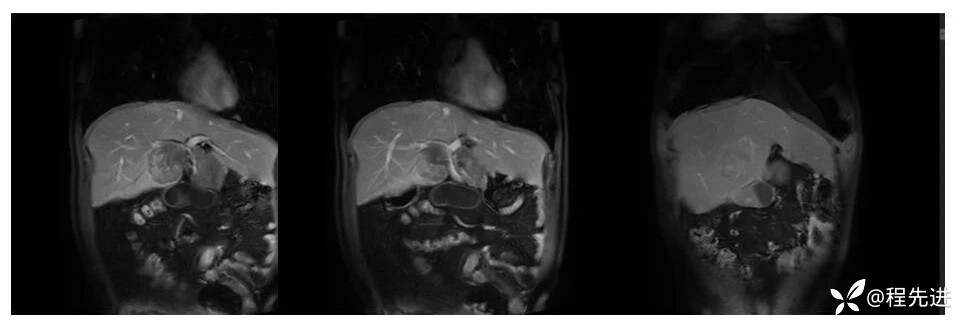

辅助检查:上腹部平扫+增强扫描提示:肝脏、脾脏、胰腺 、胃十二指肠左右倒置,脾脏形态失常,呈分叶团块状,考虑发育变异。肝左右交界区多发肿块,考虑:上皮样血管内皮瘤可能性大,或转移瘤?其它?请结合临床。脂肪肝。肝门胆管局限性扩张。胆囊折叠,壁稍增厚,慢性炎症?胰腺下方椭圆形结节,副脾?

影像检查